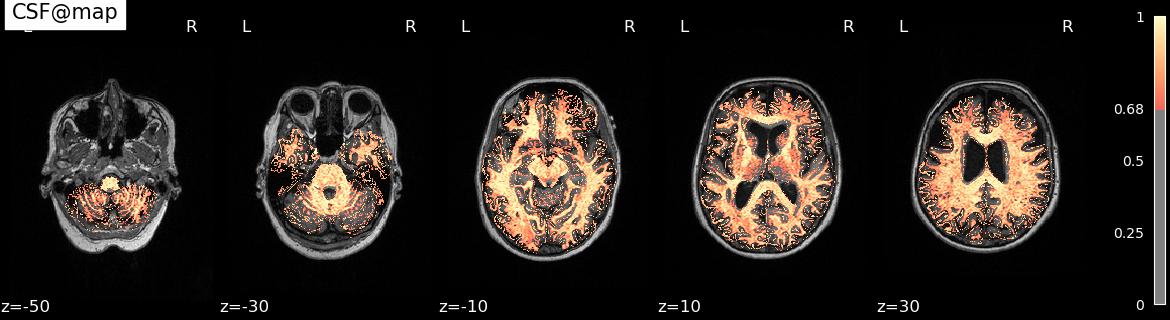

- Segmentation (using

K-meansto split GM, WM and CSF) - Visualize the results (using

nilearn)

neuro_custom python workflow.pySegmentation results are shown as cover.